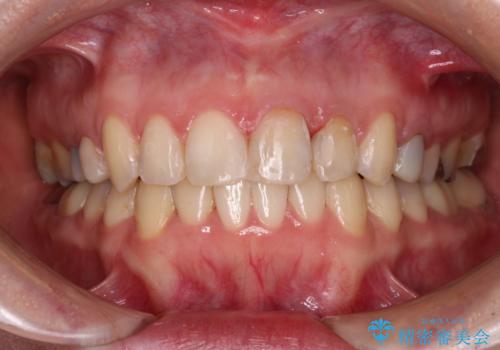

- 口元のデコボコと深い咬み合わせ(ディープバイト)を気にして来院された患者様です。

インビザラインによる上下歯列の拡大と、IPR(歯と歯の間を削る)にるスペースの獲得により、口元のデコボコとディープバイトを改善することとしました。

インビザラインは、装着していない時間がどれだけ短いかが、治療期間を大きく左右します。こちらの患者様は1日22時間以上、毎日欠かさず装着してくださったため、1年強という短期間で満足のいく歯列に整えることができました。